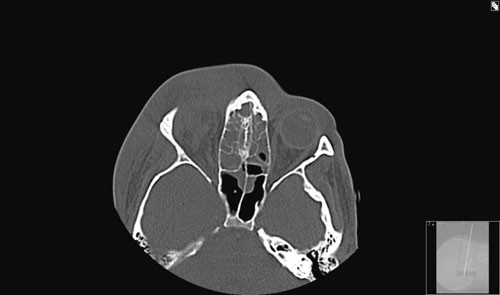

Etter ankomst regionsykehuset ble behandlingen endret etter tilsyn fra infeksjonsmedisiner. Ciprofloksacin 500 mg · 2 intravenøst erstattet gentamycin, da gentamycin har dårlig effekt ved abscesser. I tillegg økte man dosen penicillin fra 2 mill IE til 4 mill IE · 6 og metronidazol fra 500 mg · 2 til 500 mg · 3 intravenøst. CT av bihuler med kontrast viste nå abscess fra pannen og inn i mediale øyevinkel (fig 2). I tillegg så man orbital cellulitt som dislokerte bulbus frem og ned og ga pasienten en kraftig proptose av høyre øye. Det var også en kontrastoppladende oppfylning medialt oppad og baktil for bulbus.